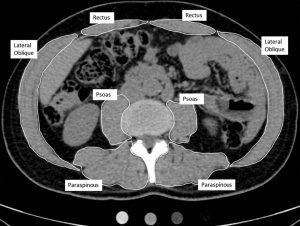

El tejido adiposo intermuscular (IMAT), un depósito de grasa ectópico que se encuentra debajo de la fascia es un fuerte predictor de la función muscular y la movilidad en adultos mayores y en una amplia variedad de enfermedades comórbidas como ictus, lesión de la médula espinal, diabetes y EPOC. IMAT también está implicado en la disfunción metabólica, como la resistencia a la insulina. Caminar, un ejercicio al alcance de casi todas las personas es una opción excelente de contribución a una vida activa, con efectos fisiológicos positivos para la salud. Desafortunadamente se ha generado una especie de “desprecio” al caminar como opción de ejercicio, al considerarse una actividad poco exigente desde un punto de vista metabólico.